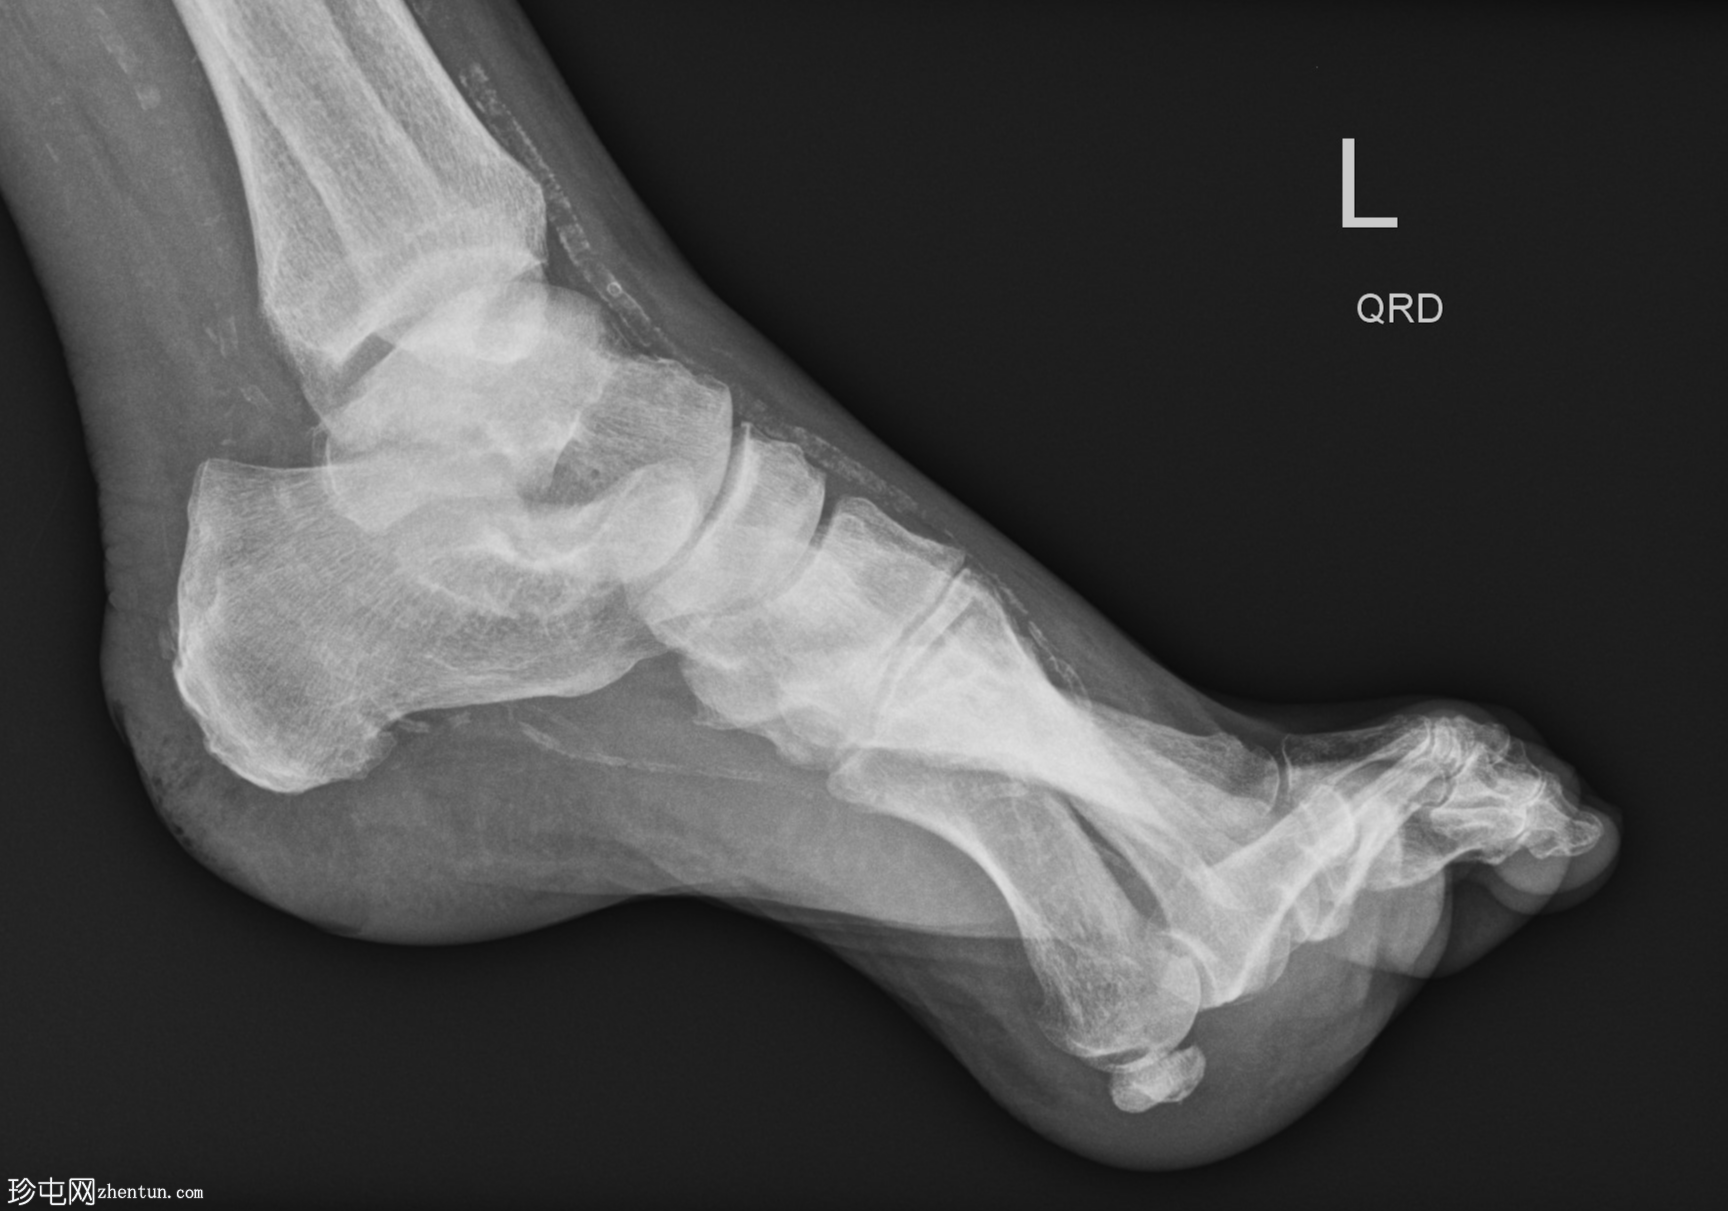

X光片

侧位片

跖趾关节爪状趾畸形

动脉钙化

爪状趾畸形是指小趾跖趾关节过度伸展,导致近端指间关节(PIP)和远端指间关节(DIP)屈曲。